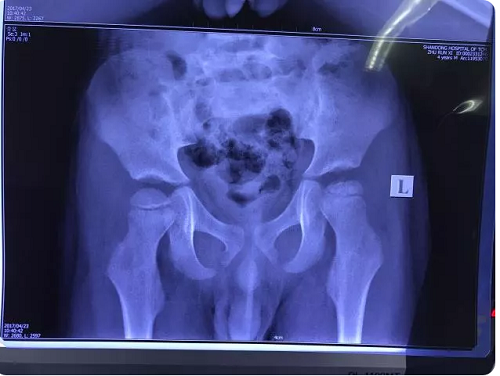

儿童股骨头坏死,又称“扁平髋”,多发于2~12岁儿童。疾病初期,患儿自觉膝痛和髋关节痛,步行不便或跛行,患侧髋不能屈伸、内收。此时...【查看详情】